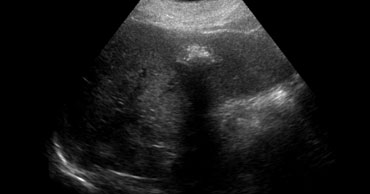

LEFT: Classic US appearance of a hemangioma.RIGHT: Also a hemangioma but now in a hyperechoic liver, so the lesion is relatively hypoechoic. Notice increased sound transmission. LEFT: Classic US appearance of a hemangioma.RIGHT: Also a hemangioma but now in a hyperechoic liver, so the lesion is relatively hypoechoic. Notice increased sound transmission.

Ultrasound

Most hemangiomas are detected with US.

If you had to pick one word to characterize a hemangioma on US, you would probably say 'hyperechoic'. You have to realize however, that this simply means that the lesion is hyperechoic to normal liver.

If the liver is hyperechoic due to steatosis, the hemangioma can appear hypoechoic (figure).

Another important feature of hemangiomas is the increased sound transmission.

This is because the lesion is made of these channels containing blood.